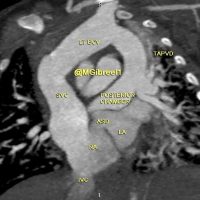

[gallery ids="16672,16675,16678,16681"] Mohamed Gibreel , FEBR (Fellowship of Egyptian Board of Radiology ) Cardiac imaging consultant at Aswan heart center -Magdi Yacoub Foundation , Egypt